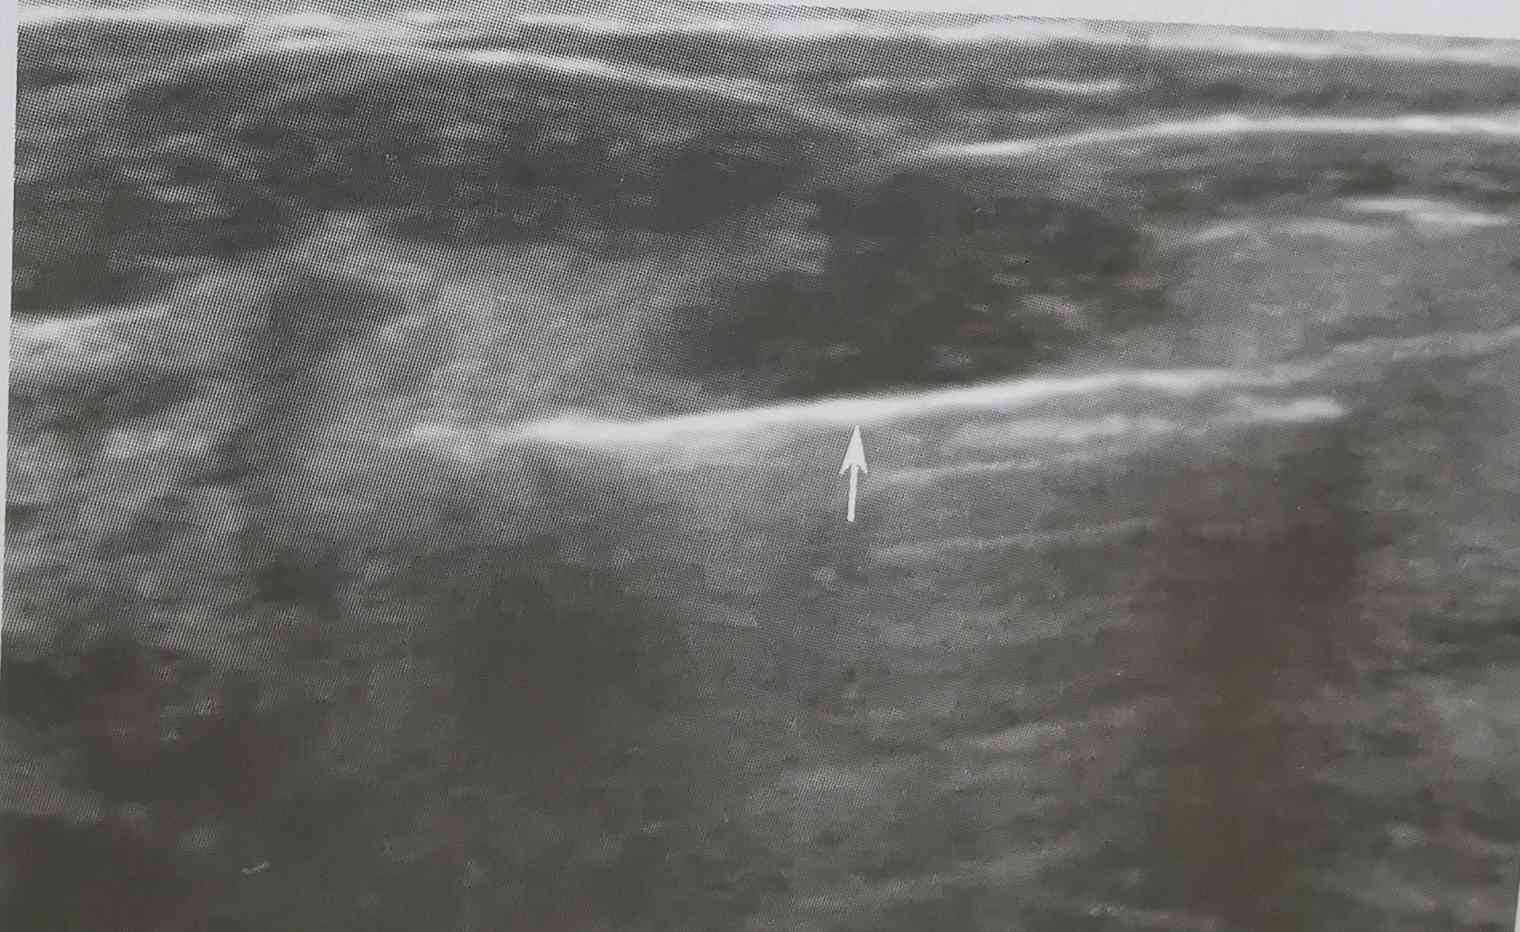

旋切过程主要在超声引导下完成(见以上图示):(1)超声显示乳腺肿物;(2)旋切刀进入肿物下方;(3)术后即刻复查,病灶已完全切除。